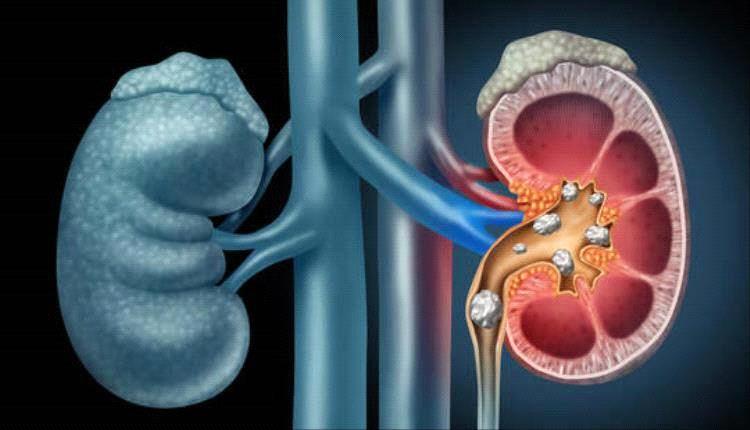

بعيدا عن ضربة الشمس والتسمم الشمسي، يمكن لأشهر الصيف الحارة أن تجلب مخاطر صحية أخرى، أهمها حصوات الكلى. ويشهد الصيف زيادة ملحوظة في الاصابة بحصوات الك